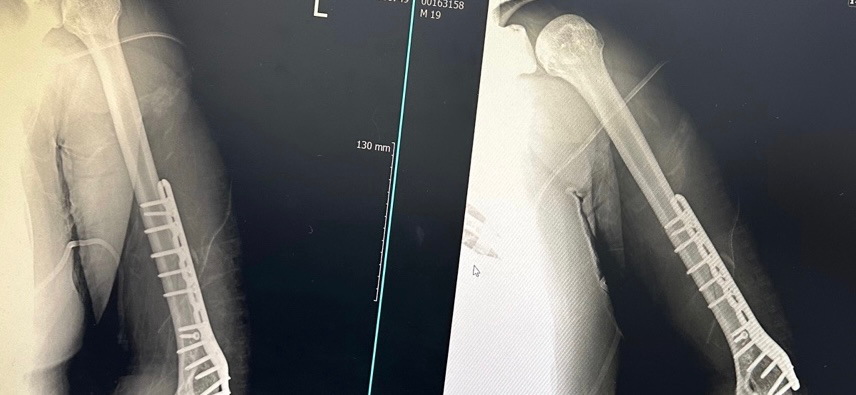

팔이 골절될 당시에 근처에 있는 신경절에 손상이 오게 되면 감각 저하등의 증상이 발생할 수 있으며, 손상 정도에 따라 수 개월동안 천천히 회복되는 경우도 있습니다. 다만 아예 감각이 없는 경우에는 손상 정도를 명확히 확인하는 것이 중요하므로 수술받으셨던 정형외과에서 재진료를 받으시는 것이 도움이 되겠습니다.